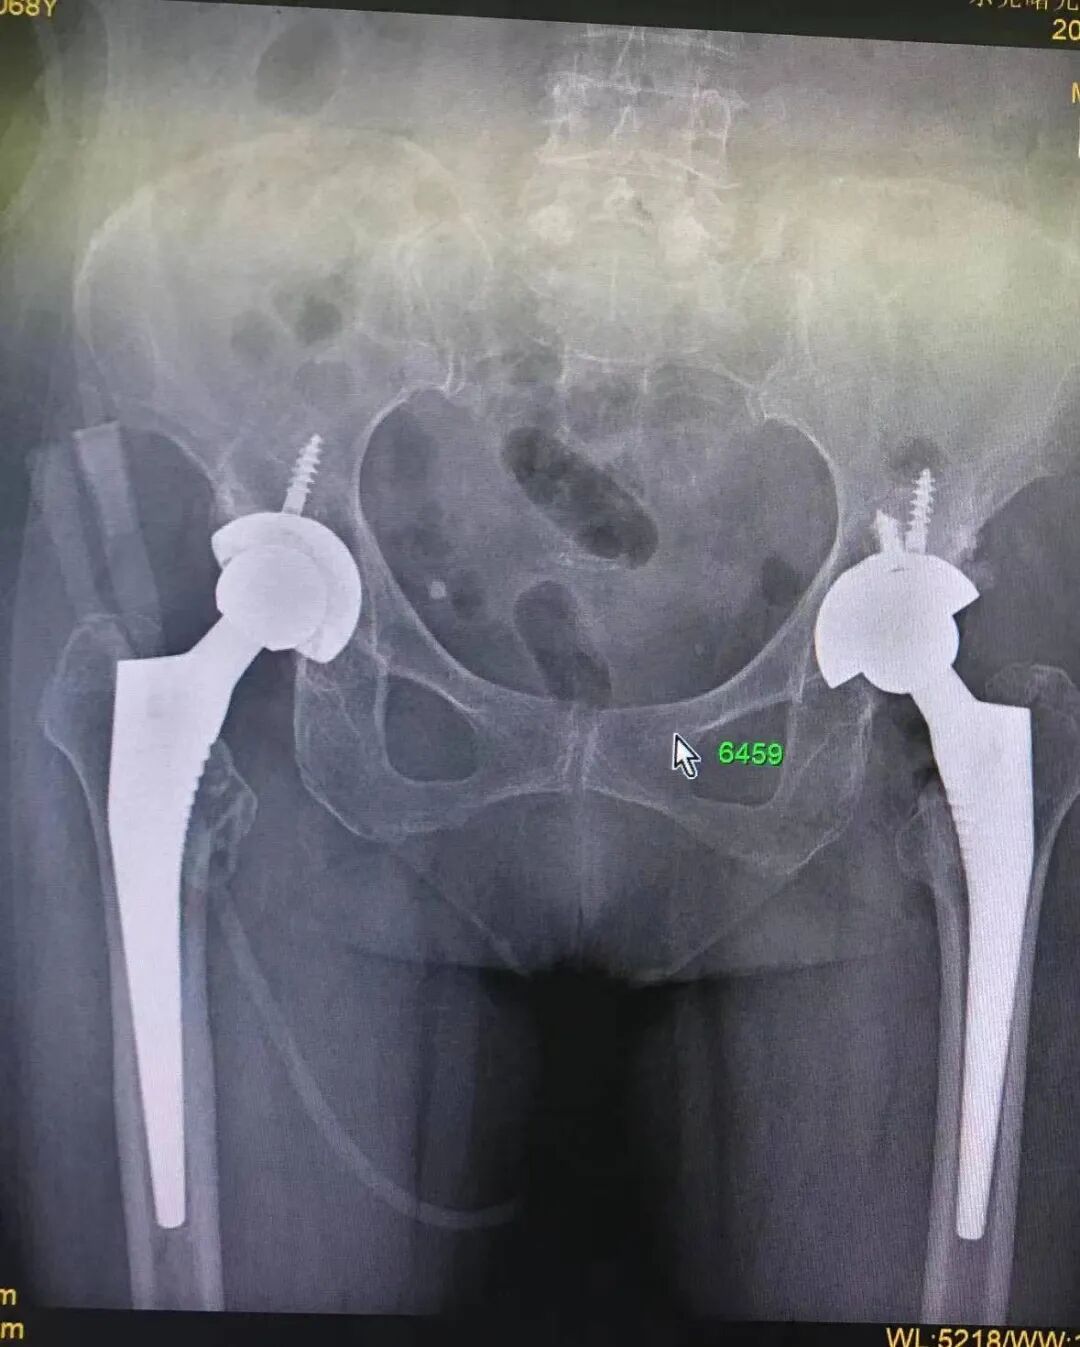

曾大姐,68岁,因腰腿、左髋部疼痛反复发作20+年,左下肢变短,跛行。两年前又开始出现右髋部疼痛。曾多处求医,间断服用中药、艾炙等效果不明显。近半年来疼痛变明显,站立、行走困难,严重影响日常生活及睡眠。去当地社区医院就诊,效果仍不佳。后经朋友介绍,于5月10号来我院就诊。门诊以“双股骨头坏死,腰椎间盘突出”收入骨科住院治疗。

DR示:双股骨头坏死、变形。

(图 入院时的DX影像)

因病程时间长,双侧股骨头坏死变形,左侧髋臼结构破坏,骨科病情严重。入院后骨科主任贺胜利便亲自担任了她的主管医生。他在为曾大姐治疗缓解腰椎盘突出引起的神经压迫症状的同时,积极申请相关科室专家会诊,为尽可能解除术中及术后可能出现的隐患问题,经大家充分讨论分析,最后,决定分两次进行人工全髋关节置换手术。